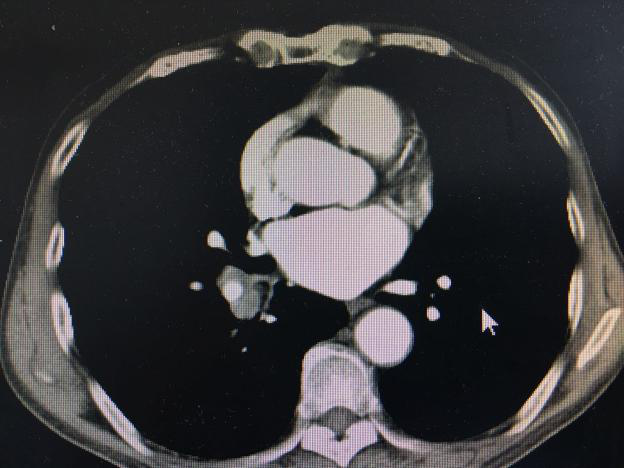

王大爷今年近80岁,因病住院,住院后行胸部强化CT提示右肺门占位:(见下图)

因病变部位靠近肺门,外周穿刺气胸、出血风险均较大,气管镜检查是最合适检查诊断方案,患者体质差,气管镜检查过程风险大,同时患者抵抗情绪严重,拒绝检查,不能取到病理,无法进行下一步治疗,家属焦急万分。肺病贾在金主任、于得海主任、麻醉手术科杜妍主任及科室医务人员联合进行讨论。